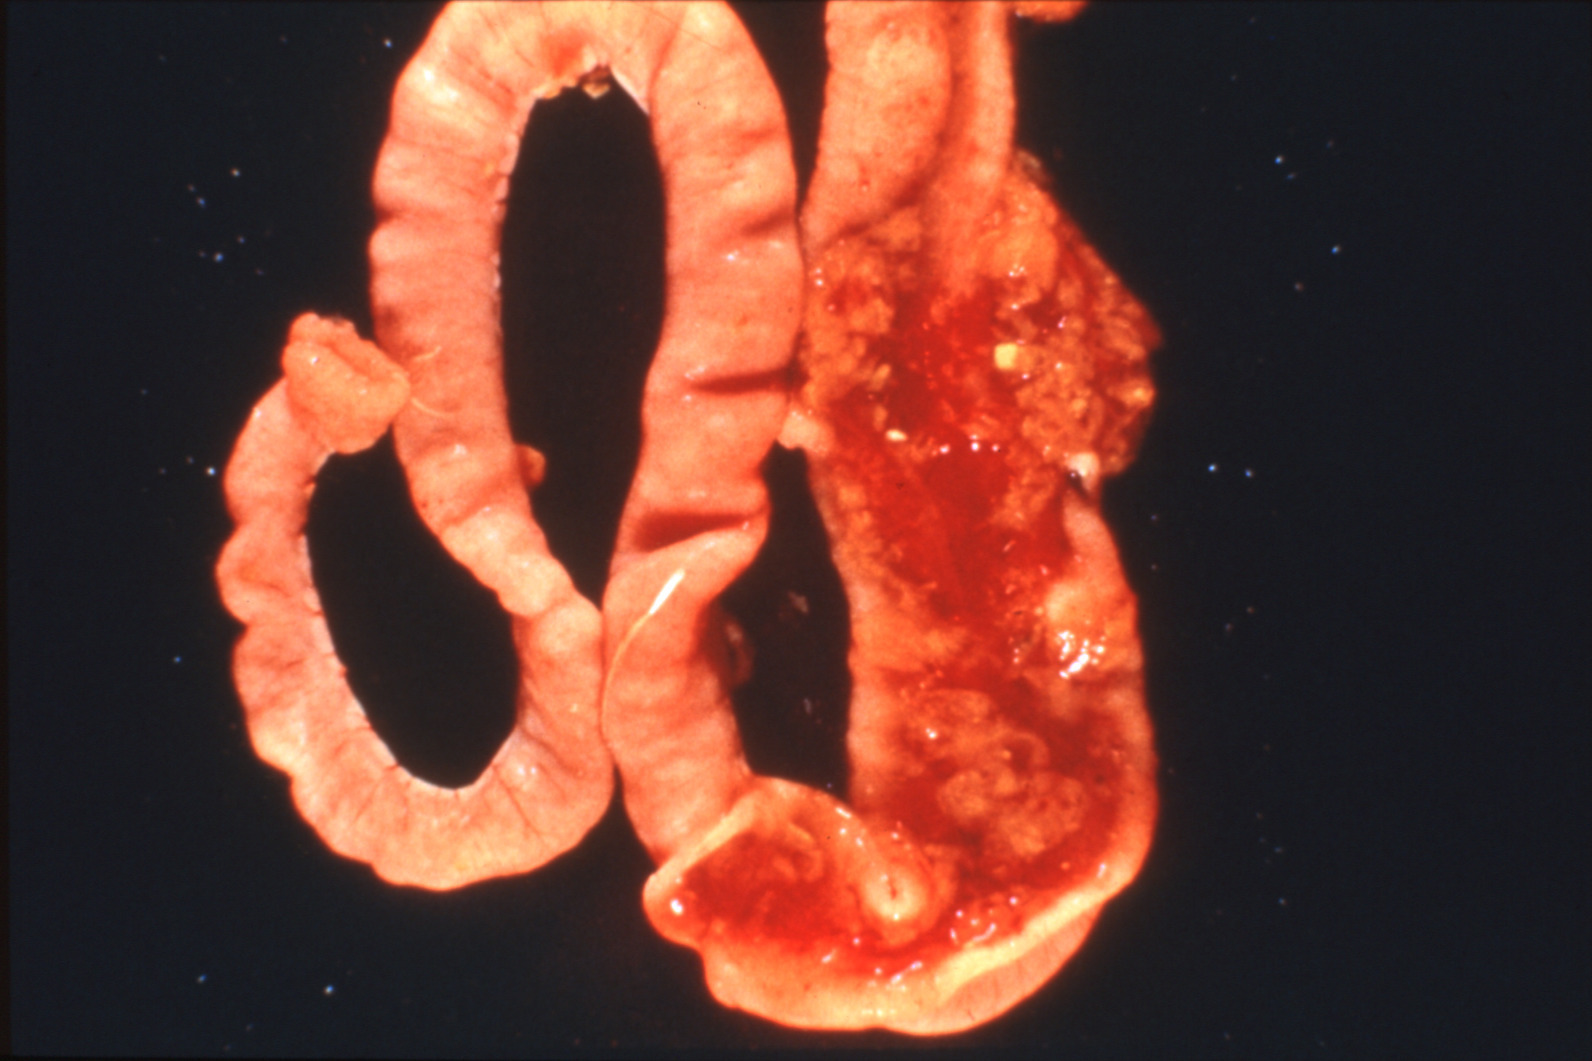

Coccidiosis in chickens and turkeys (slide study set no. 7)

Avian coccidiosis Avian medicine Chickens--Diseases Turkeys--Diseases